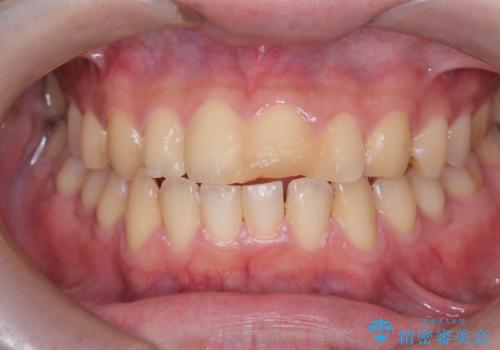

サーフィンで前歯をぶつけて歯が欠けた|かかりつけ医で治療困難と言われ当院へ来院|VPT(生活歯髄療法)で神経を保存|前歯の見た目も改善

- 歯冠破折により点状露髄を認めました。破折から1週間以内であったこと、また歯髄診断により生活反応が良好で保存可能と判断したため、VPT(生活歯髄療法)を行い神経の保存を試みました。